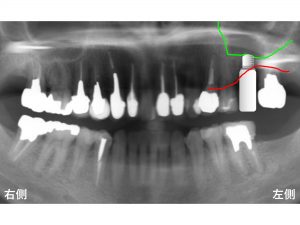

以下が初診時です。

上顎左側奥から2番目が欠損しています。

骨が吸収しているのです。

わかりやすいように骨吸収の状態を線でかいて見ます。

以下の青線が骨吸収する前の元々の骨の位置です。

現在の骨吸収した状態が以下の赤線です。

そして緑線が上顎洞の一番下の部分です。

この3つの線を組み合わせたのが以下です。